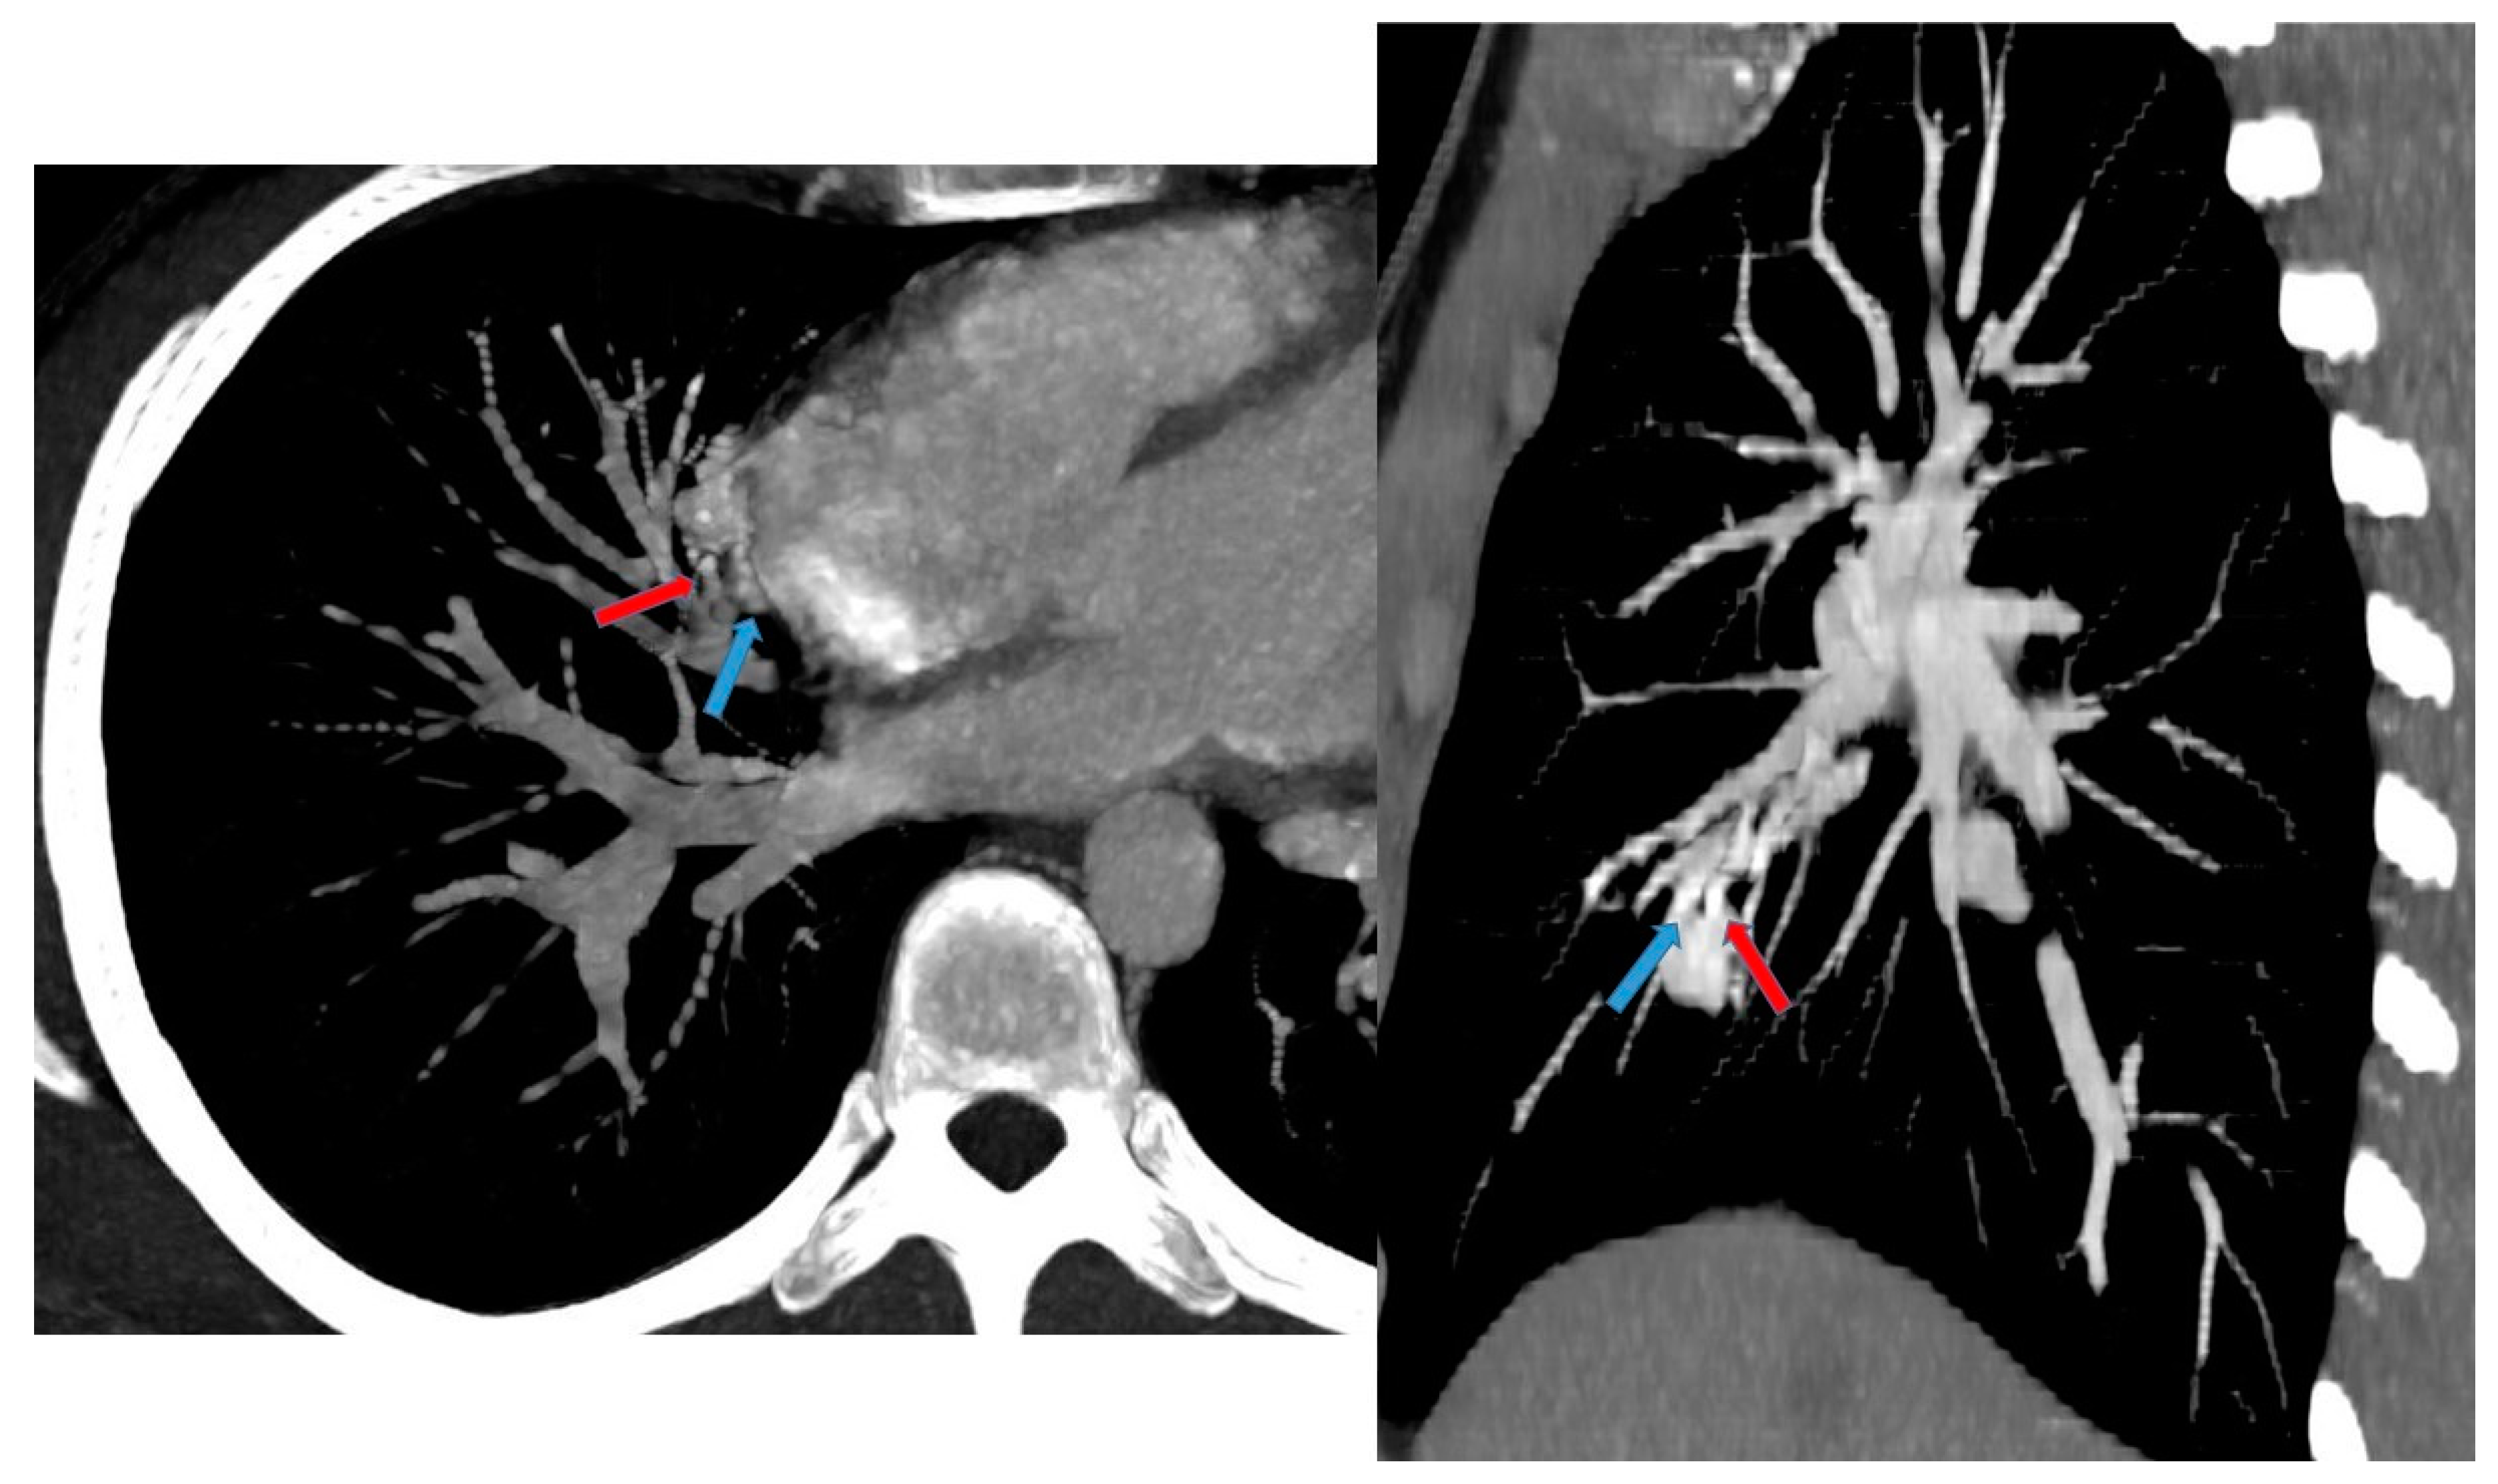

3.6.1. Pulmonary Sequestration

| Intralobar Type | Extralobar Type | |

|---|---|---|

| Incidence | 75% | 25% |

| Cause | acquired or congenital | congenital |

| Timing of Diagnosis | childhood or adulthood | Prenatal–neonatal period |

| Pleural Investment | within lobe without its own pleura | with its own lung pleura |

| Arterial Supply | thoracic or abdominal aorta | abdominal aorta |

| Venous Drainage | pulmonary venous system | systemic venous system |

| Association with Other Congenital Anomalies | rare | common |